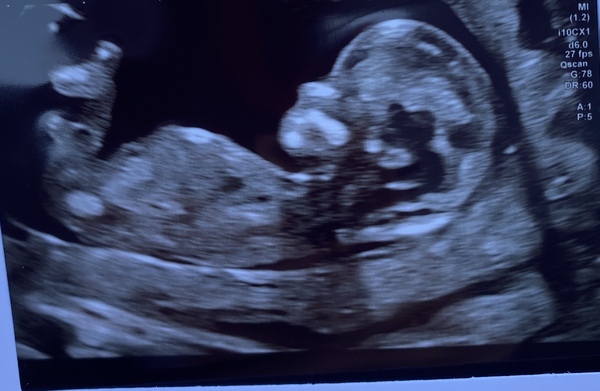

Kt1111 · 26/08/2021 21:23

Hi ladies hope You’re all doing well. Just thought I’d update after my Scan as I feelLike you ladies all kept me going when trying to Conceive. I’m 12 weeks and 6 days. Due 4th March. The clearest scan ever and all going well, hoping for good news for you ladies too x

Giraffe25 · 26/08/2021 21:32

Ah so lovely!!!!! Congrats @Kt1111 I'm absolutely delighted for you 🥰

Goingoutofmymind21 · 26/08/2021 21:40

@Kt1111 ahh lovely! That’s super clear :)